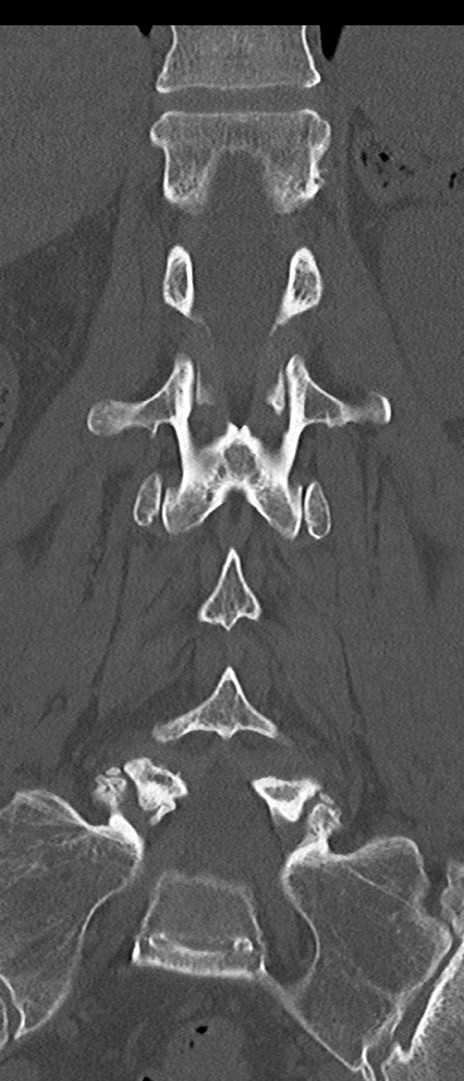

腰椎CT

横断像